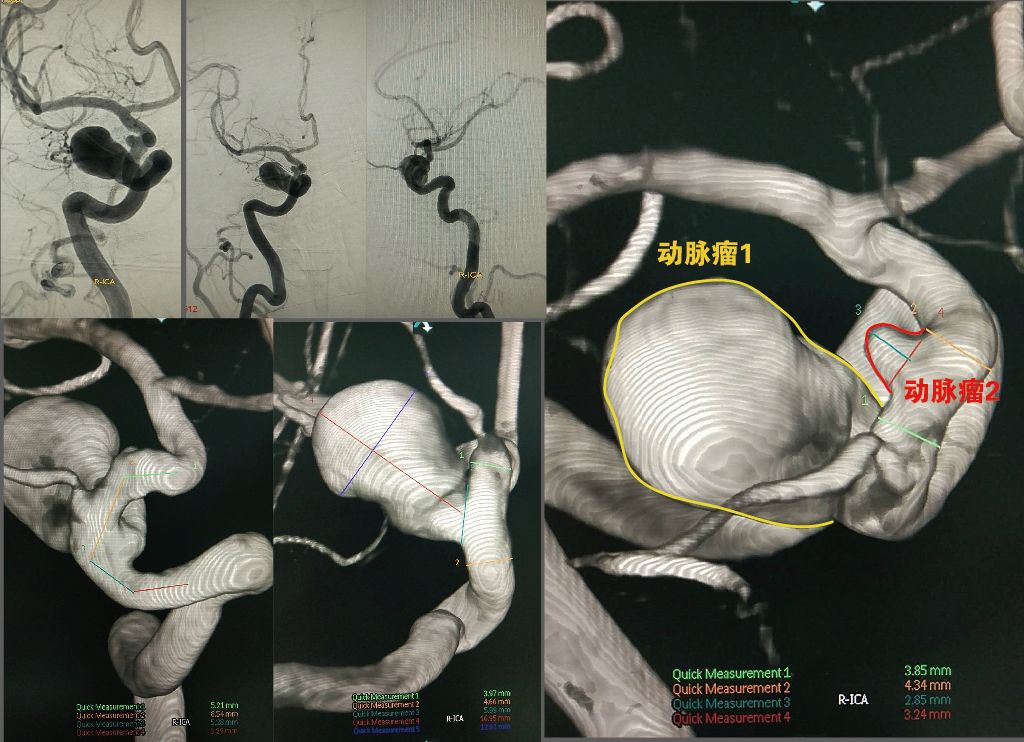

右侧床突段相邻1大1小两个动脉瘤,大瘤体16.95mm*12.61mm,瘤颈5.99mm,载瘤动脉近远端最大径约3.97mm,4.66mm; 小瘤体2.85mm*3.24mm, 载瘤动脉近远端最大径约4.34mm,3.24mm;Tubridge拟覆盖范围需跨越两个瘤颈,长度约24.32mm。

术中,三维重建多角度测量,Tubridge远端锚定的载瘤动脉直径约3.99mm,近端约4.66mm,拟覆盖载瘤动脉长度约29.29mm。考虑到3D测量存在误差,同时参照2D影像图并以Navien直径(2.12mm)作为参照,doublecheck载瘤血管远近端直径,为3.8mm,4.5mm。

反复测量后,最终选择Tubridge4035的型号。因为4.0mm直径的支架,自然态直径+0.5,即为4.5mm,满足近端血管直径的同时又能兼顾远端3.8mm的血管直径,支架远端打开更容易。然而,4.0mm直径的支架放置在4.5mm直径的血管里会有1/3短缩,当支架跨越瘤颈时,也会存在一定程度的“膨出”,所以基于安全的的考虑,支架长度选择略长一些,为35mm。